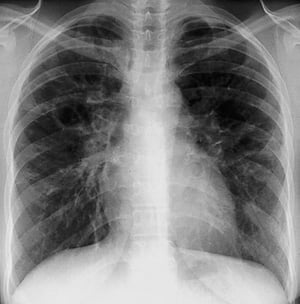

Sarcoidosi (stadio III)

Opacità interstiziali diffuse senza adenopatia ilare nello stadio III della sarcoidosi.

By permission of the publisher. Da Tanoue L, Elias J. In Bone's Atlas of Pulmonary and Critical Care Medicine. Edited by J Crapo. Philadelphia, Current Medicine, 2005.